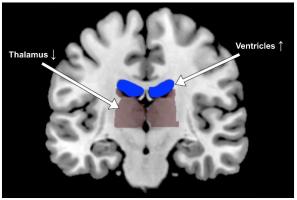

DÉSHYDRATATION : Elle assèche la cognition !

Actualité publiée le 30/12/2019DÉSHYDRATATION : Elle assèche aussi la cognition

DÉSHYDRATATION : Notre esprit sèche aussi